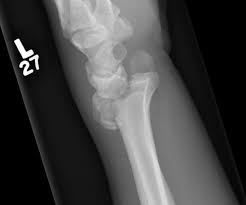

• Die-punch fx

• Depressed fracture of the lunate fossa of the articular surface of the distal radius